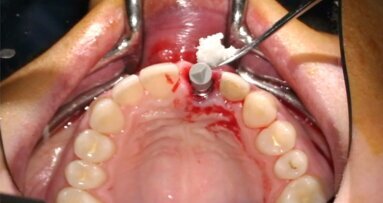

In questo articolo presentiamo un caso clinico che dimostra come il posizionamento improprio di un impianto può rendere impossibile la riabilitazione protesica, che richiede una nuova pianificazione chirurgica e riabilitativa per ottenere l’estetica desiderata. La paziente si presenta alla nostra osservazione con una riabilitazione protesica incongrua, con flangia in resina, a supporto dentale ed implantare, con la presenza di un impianto in posizione 2.1 vestibolarizzato e con l’emergenza nel fornice, in mucosa alveolare. Dalla valutazione della Tac si evince la posizione errata dell’impianto e la perdita consistente in senso trasversale della compagine ossea (Figg. 1, 2). Pertanto si opta per il seguente piano di trattamento che prevede: rimozione dell’impianto e preparazione protesica dell’elemento 2.3, confezionamento di un primo provvisorio a supporto dentale che servirà a guidare la guarigione dei tessuti (Figg. 3-7). A distanza di 4 mesi si procede a un innesto epitelio connettivale libero con prelievo dal palato per compensare il gap dei tessuti molli in senso trasversale, quindi viene ribasato il provvisorio in modo tale da favorire la guarigione dei tessuti (Figg. 8-11). A 9 mesi dalla maturazione dei tessuti si procede alla finalizzazione protesica fissa a supporto dentale (Figg. 12-14).

Fig. 5 - Rimozione atraumatica dell’impianto con l’utilizzo dello svitatore.

Fig. 8 - Innesto di epitelio connettivale libero dopo 4 mesi dalla guarigione del sito implantare.

Fig. 9 - Sede del prelievo epitelio connettivale dal palato.